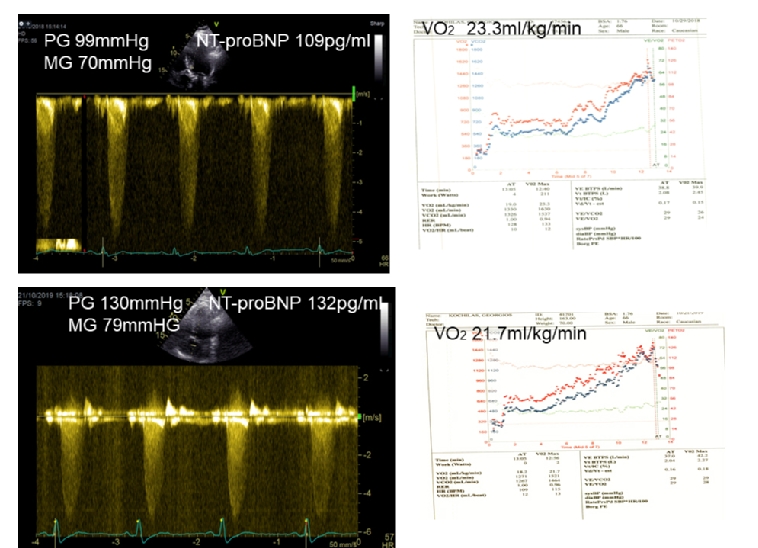

The inability of patients >70 years of age to undergo exercise testing or cardiopulmonary exercise testing makes the assessment of symptoms controversial and may lead clinicians to suggest intervention at a premature stage without being convinced that this is a timely decision [16]. Interestingly, natriuretic peptides can be used to differentiate heart failure from chronic obstructive pulmonary disease (COPD) in patients presenting with SOB [17]. However, the mechanism of this brain natriuretic peptide (BNP) elevation has not been defined, as plasma levels of natriuretic peptides can increase during exercise in patients with AS. BNP has therefore become an important tool to connect symptomatic status, exercise tolerance, ventricular function and prognosis (Figure 1). In a study of 130 patients with severe AS, it was shown that NtBNP was the only independent predictor of outcome [18].

210_Karatasakis_Figure 1_Clinical features of aortic stenosis the need for exercise testing a general introduction.jpg

Upper Panel: Baseline

Lower Panel: Changes in 12 months’ time. Peak gradient increased by 31 mmHg, O2 consumption decreased from 23.3 ml/kg/min to 21.7 ml/kg/min and NT-proBNP increased from 109 pg/ml to 132 pg/ml (upper normal 125 pg/ml).